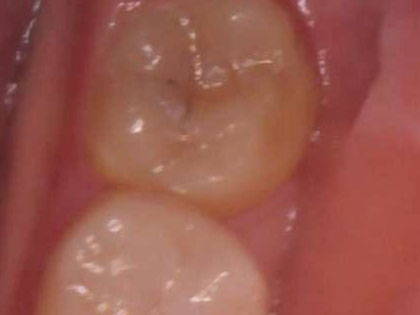

• 親知らずの抜歯術前1

• 親知らずが虫歯になっており、歯ブラシが普段から当たってなく穴があいて虫歯になっています。